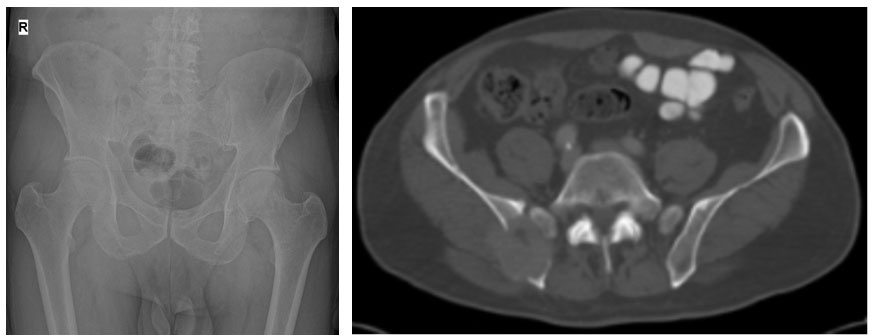

Ameliyat öncesi: Röntgen ve tomografide sağ leğen kemiği arka kısımda kemik harabiyeti ve kemiğin dışına taşan tümör dokusu görülmekte